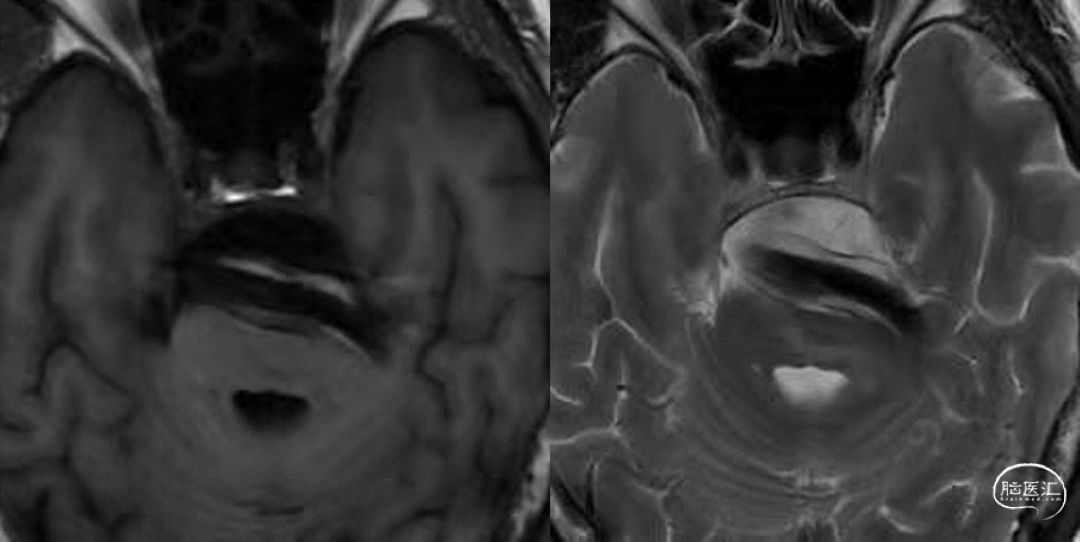

患者术前即口服阿司匹林100mg 1/日,替格瑞洛90mg 2/日,术前聚集率分别为8.6%和19.5%;术中释放第一枚LEO+支架后予以静脉推注替罗非班5ml,并5ml/h维持泵入;术后即刻患者情况良好。替罗非班逐步减量至3ml/h时,患者出现复视,构音不清,四肢无力及共济失调表现,mRS:4分;替罗非班加量至5ml/h后症状缓解;维持24小时后再次减量,至3ml/h时再次出现上述表现。后予以应用低分子肝素,5000iu 2/日,症状改善,3日后更替为达比加群酯110mg 2/日(表1)。此后患者神经系统情况稳定,复查MR未见新发梗死,可见支架内流空良好,支架外血流缓慢(图3),术后10天出院,mRS:3分。

图3